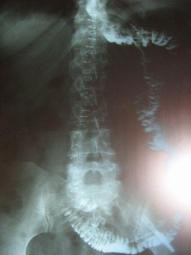

Estudio radiológico previo a inicio de alimentación